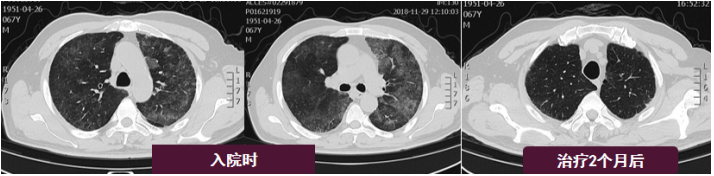

在常规气管镜、适当镇静情况下,通过局部麻醉缓慢完成TBLB操作。患者肺泡灌洗液脱落细胞阴性,肺泡灌洗液未查到癌细胞。最终经活检证实为黏液腺癌。(5)冷冻肺活检 & TBLB:冷冻肺活检也是近年来开展比较多的一项技术,尤其在弥漫性间质性肺疾病的诊断中发挥了重要作用。此项技术不仅可以在手术室完成,也可以在床旁完成。病例:男性,67岁,鼻塞伴双上肢肌肉酸痛2天,呼吸困难1天。血常规:WBC 14.48×109/L,NEU% 87.5%,RBC 5.34×1012/L,Hb 117 g/L,PLT 99×109/L;血气分析提示Ⅰ型呼吸衰竭。入院即刻床旁气管镜检查。BALF和保护毛刷培养均阴性,病原微生物NGS结果阴性,TBLB病理提示慢性炎症。治疗前后胸部CT如图4所示。呼吸内镜下常用的介入技术包括:气管支架植入/球囊扩张等机械性迅速改善气道通气/畅的能力,清理气道内异物、分泌物、止血技术,经口/鼻气管镜引导下气管插管,电切刀/电凝/氩等离子体(APC)/激光等热消融技术,冷冻/药物注射等。(1)治疗性肺泡灌洗:患者女性,79岁,溺水10小时,气管插管下于2019年3月15日7:30 pm转入RICU。入院后迅速进行肺泡灌洗,清理肺内恶性分泌物,患者得到及时有效的救治。患者胸片变化如图5所示。(2)威胁生命大咯血救治:吸引清除气管内凝血块,最大限度地保障气道通畅和有效的气体交换;对于威胁生命的大咯血,支气管镜可在其他特定手段干预之前,迅速提供有价值的治疗性止血措施;气管镜处理时机:84%的介入肺脏病医生会在咯血24 h内行气管镜检查。对于大咯血,有两种方式治疗:局部治疗(冰盐水灌注, 肾上腺素盐水, 血管加压素, 凝血酶纤维蛋白原复合物, 氨甲环酸, 氧化再生纤维素医用蛋白凝胶等)和气管腔内治疗[Fogarty球囊封堵器, 硅胶塞, 热消融技术(激光、APC、冷冻),双腔气管插管]。可以在短期内尽可能地控制出血,为后续治疗争取时间。(3)快速解除气道梗阻—气管支架植入/球囊扩张等:气管内肿瘤或气管食管瘘患者引发严重呼吸困难,气管支架是重要的解决方法之一。对于急症患者,支架置入的推广和培训相对比较容易。临床中还能会通过球囊扩张等方法来解决一部分气道的问题。(4)气管镜引导下经皮扩张气道造口术(PDT):1985年Ciaglia等报道,PDT目前已经应用已经越来越广。与外科相比,PDT减少了出血,缩短了手术操作时间,降低了医疗费用,减少了切口感染机会。此项技术的并发症发生率在5%左右,但仍有致命性并发症的发生风险。一项研究分析了70例与PDT相关的死亡病例,结果发现,PDT相关死亡率为0.17%,致死性并发症主要是血管损伤和气道相关并发症。因此建议:认真筛选患者,由气管镜引导下行PDT。(5)取气管内异物:气管内取异物相对简单,但对于手术耐受性差的患者仍然存在一定风险,注意选择适宜的器械和技术取异物,做好并发症的应对。(1)呼吸内镜介入技术的规范化培训和推广:保证质量以及使结果同质化。例如:肺泡灌洗如何提高阳性率?如何预防和避免并发症?是否真正把握了合适的适应证和禁忌证——哪些患者需要做,哪些患者不需要做?是否真正明晰了操作的目的和价值?如何规范化放置急症气管支架?如何处理出血等并发症?如何保证和监管各种介入操作技术的质量?一项针对麻醉医师的全国性横断面研究纳入了2016年10月27日至2016年11月27日期间1935份关于困难气道处理的问卷回复,当出现意外困难气道时,63%的10年以下麻醉医师和65%的10年以上麻醉医师会在尝试1~2次后寻求帮助(P=0.000)。超过70%的受访者表示他们更喜欢套管环甲膜切开术来处理紧急气道;受访麻醉师在困难气道评估方面存在培训缺口,培训和使用FONA应急技能,促进国内外气道管理指南的使用;应对年轻医生进行更多的气道管理理论和技能培训,以提高他们的气道管理技能。以色列一项ICU内气道管理问卷调查涉及20个ICU,应答率为70%(20个ICU中有14个),其中71%的ICU采用ASA算法评估困难气道,气管镜下插管在以下两种情况使用频率明显高于其他方法:78%的困难气道和64%的颈椎损伤(P<0.0001);只有43%的单位报告召开了质量保证会议。69%的单位负责人对他们的气道管理策略感到满意。(2)创新与发展:需要是发展的动力,实践是发展的基础,创新是发展的源泉。①器械的创新:需要更为清晰价廉的不同型号的床旁内镜的研发,包括一次性内镜;在临床发现问题并反馈给技术人员,重视医工结合,在临床中寻找新的切点,有更多呼吸介入相关产品的发明和转化。②技术的创新:例如经皮气切技术的不断发展,在新技术的辅助下,使可视化程度不断增加,进一步提高技术的成功率和安全性。(3)呼吸重症团队人才缺口:注重人才建设,需要建立强大的医师队伍、治疗师队伍、护理队伍、护工队伍等。呼吸内镜介入技术与呼吸危重症医学密不可分,呼吸内镜介入技术是呼吸危重症医学发展中不可或缺的关键性技术之一,呼吸危重症医学亦是呼吸内镜介入开展和创新的最后一道安全防线。临床常用介入性诊断和治疗技术包括TBNA、TBLB、冷冻肺活检、肺泡灌洗、支架置入、冷热消融等技术,它们在呼吸危重症患者的救治中有重要的应用价值。当下仍然需要加强呼吸内镜介入技术规范化培训以及专科化呼吸危重症人才队伍的建设。[1] De Jong A, Myatra SN, Roca O, et al. How to improve intubation in the intensive care unit. Update on knowledge and devices[J]. Intensive Care Med, 2022, 48(10):1287-1298. [2] Alhomary M, Ramadan E, Curran E, et al. Videolaryngoscopy vs. fibreoptic bronchoscopy for awake tracheal intubation: a systematic review and meta-analysis[J]. Anaesthesia, 2018, 73(9):1151-1161. [3] Revel MP, Fournier LS, Hennebicque AS, et al. Can CT Replace Bronchoscopy in the Detection of the Site and Cause of Bleeding in Patients with Large or Massive Hemoptysis?[J]. AJR Am J Roentgenol, 2002, 179:1217-1224. [4] Torbiarczyk JM, Sobczak PA, Torbiarczyk KK, et al. Is bronchoscopy always justified in diagnosis of haemoptysis?[J]. Adv Respir Med, 2018, 86:13-16.[5] Hsiao EI, Kirsch CM, Kagawa FT, et al. Utility of Fiberoptic Bronchoscopy Before Bronchial Artery Embolization for Massive Hemoptysis[J]. AJR Am J Roentgenol, 2001, 177:861-867.[6] Charya AV, Holden VK, Pickering EM. Management of life-threatening hemoptysis in the ICU[J]. J Thorac Dis, 2021, 13(8):5139-5158.[7] Haponik EF, Chin R. Hemoptysis: Clinicians’ Perspectives[J]. Chest, 1990, 97:469-475.[8] Ma G, Yang R, Gu B, et al. Tracheal stent placement provides opportunity for subsequent anti-cancer therapy for cancer patients with malignant respiratory complications[J]. Ann Palliat Med, 2021, 10(2):1042-1049.[9] Ciaglia P, Firsching R, Syniec C. Elective percutaneous dilational tracheostomy[J]. Chest, 1985, 87(6):715-719.[10] Ghattas C, Alsunaid S, Pickering EM, et al. State of the art: percutaneous tracheostomy in the intensive care unit[J]. J Thorac Dis, 2021, 13(8):5261-5276.[11] Abbott F, Ortega M, Bravo S, et al. Can we improve teaching and learning of percutaneous dilatational tracheostomy's bronchoscopic guidance?[J]. SAGE Open Med, 2021, ;9:20503121211002321. [12] Bajaj D, Sachdeva A, Deepak D. Foreign body aspiration[J]. J Thorac Dis, 2021, 13(8):5159-5175.[13] Ayats-Vidal R, Vásquez-Pérez A, Gallego-Díaz M, et al. Successful removal of distal persistent foreign body airway with CO2 cryotherapy in a child[J]. Respir Med Case Rep, 2022, 36:101594. [14] Bajaj D, Sachdeva A, Deepak D. Foreign body aspiration[J]. J Thorac Dis, 2021, 13(8):5159-5175. [15] Liu HH, Wang Y, Zhong M, et al. Managing the difficult airway: A survey of doctors with different seniority in China[J]. Medicine (Baltimore), 2021, 100(38):e27181.[16] Haviv Y, Ezri T, Boaz M, et al. Airway management practices in adult intensive care units in Israel: a national survey[J]. J Clin Monit Comput, 2012, 26(6):415-421.